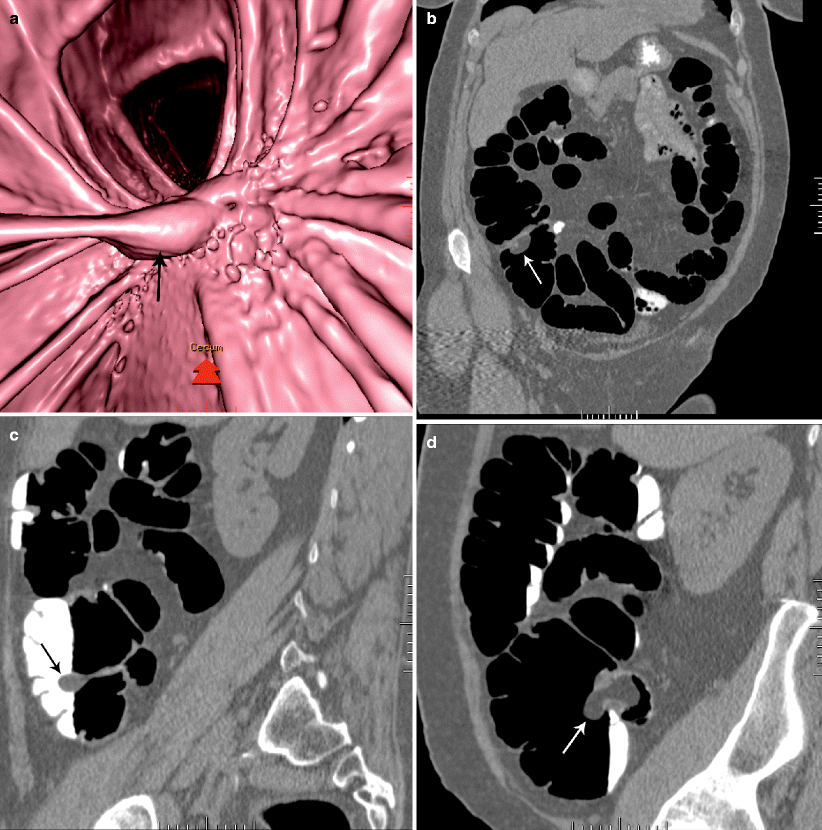

(a) Medially placed ileocecal valve (arrow). (b) Dilated, twisted cecum What Causes The Ileocecal Valve To Close signs and symptoms of ileocecal valve disorder are pain in the. Basic dysfunction of the ileocecal valve can cause backflow of cecal contents into the ileum. first, you can hold the valve shut for several minutes. the ileocecal valve controls the flow of digested food when it is time for it to leave the small intestine, and. What Causes The Ileocecal Valve To Close.